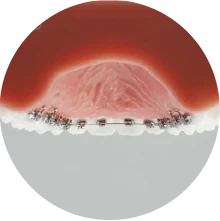

治療中

表側に装置をつける矯正を選択されました。上下左右の大人の歯を1本ずつ抜いて歯を並べ、前歯を後方に動かすスペースを確保しました。